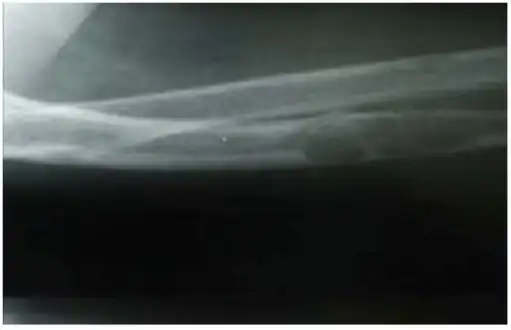

Lateral X-ray of the right radioulna showing osteitis fibrosa cystica lesion of ulna diaphysis with a pathologic fracture

| Osteitis fibrosa cystica of the tibia. Arrows point to the brown tumors which are typically present in bones of people with OFC. | |